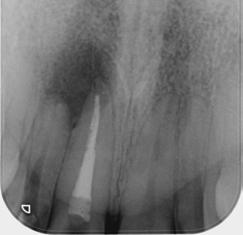

This is not a “Terminal Dentition”. It is interesting to see the increase in patients being advised that Periodontitis is not treatable or that treatment is somehow expensive and ongoing maintenance is difficult/unachievable. These patients are usually advised to receive implant treatment as an alternative.

This patient first presented in 2016 at the age of 33 years. He was a former smoker (quit two years prior to the initial presentation). He presented with generalised deep pocketing and advanced loss of attachment.

Radiographic assessment showed generalised moderate to advanced bone loss with most teeth showing bone loss to more than 50% of the root length. Given the established loss of attachment in relation to his relatively young age, this patient was diagnosed with generalised aggressive periodontitis. According to the 2017 Classification of Periodontal Disease, he would be Stage III, Grade C Periodontitis.

The patient was managed with non-surgical periodontal debridement. Two months later, he presented with an encouraging reduction in periodontal probing depth (PPD). There were 85% sites with PPD 1-3mm, 15% sites with PPD 4-5mm and no sites with residual PPD > 6mm. The patient showed excellent plaque control measures and his bleeding on probing score was 1%. The patient has been placed on a six-monthly periodontal maintenance program with the periodontist. He also sees his general dentist once annually. The OPG images dated 2016 and

2023 show stable bone levels with no evidence of further bone loss.

The patient had orthodontic treatment between 2018-2020 to address the flaring and spacing of his teeth, which was a cosmetic concern to him (orthodontic treatment done by Dr Frank Furfaro). Long-term evidence shows that we, as dental clinicians, are not accurate at determining the prognosis of periodontally compromised teeth (McGuire 1996). We may also be hasty at labelling such teeth as “hopeless”. The threshold at which we

decide to extract teeth due to periodontal disease may be too low (Splieth 2002). There is no evidence on the other hand that dental implants have longer survival or less complications or better cost compared to periodontally treated teeth.